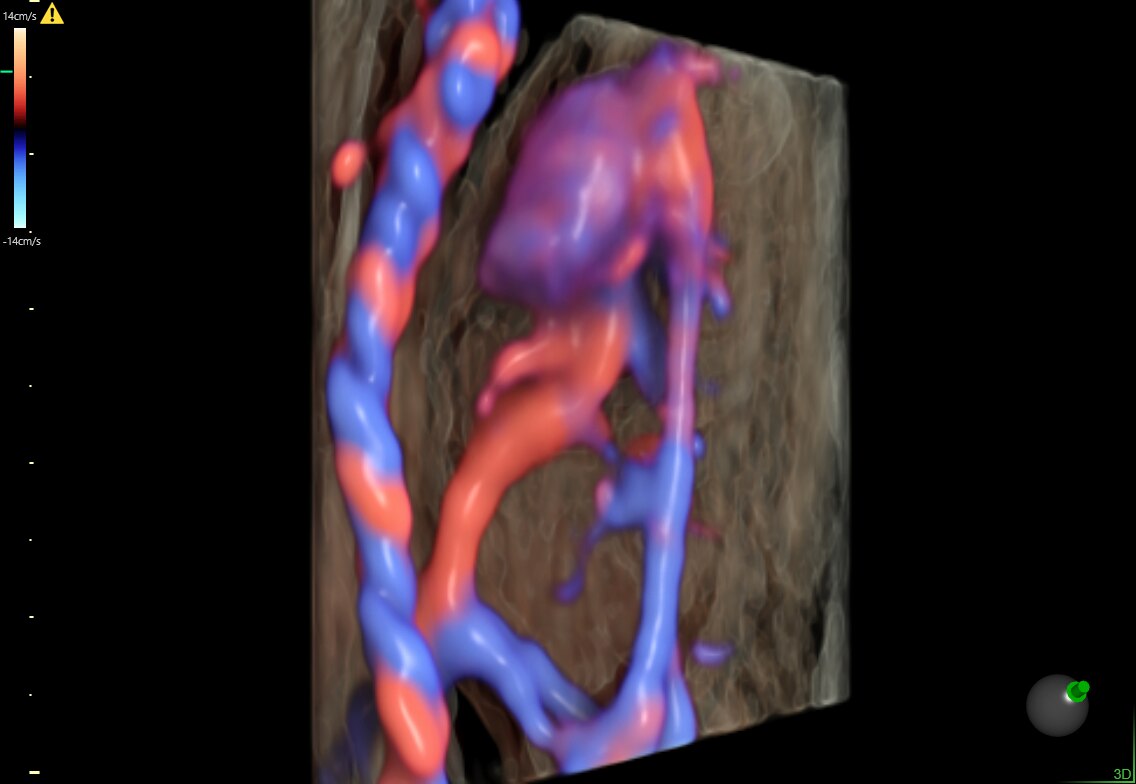

Fetus with HDlive™ generated with SonoRenderlive